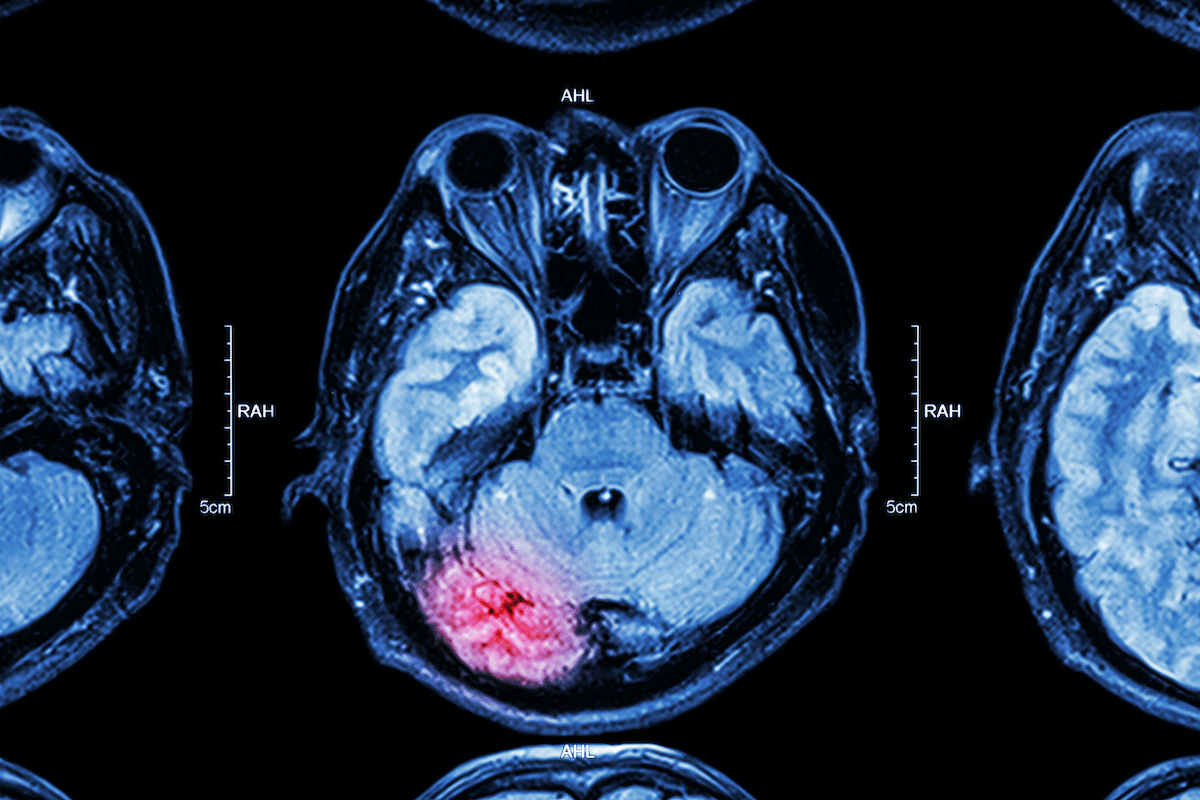

Neuroimaging is a big part of diagnosing brain vasculitis. MRI (Magnetic Resonance Imaging) and angiography show blood vessel problems. Blood tests and lumbar punctures help rule out other conditions.

It’s key to understand how brain vasculitis and stroke are connected. Brain vasculitis is an inflammatory condition that affects the brain’s blood vessels. It can greatly increase the risk of stroke. This section will look at the link between brain vasculitis and stroke, focusing on ischemic and hemorrhagic strokes. We’ll also talk about why early detection is so important.

Ischemic stroke happens when an artery to the brain gets blocked. This blockage is often caused by a blood clot or fatty deposit. In brain vasculitis, inflammation can cause blood vessels to narrow or block. This makes ischemic stroke a big risk for those with untreated or severe brain vasculitis. We’ll dive into why this is and what it means for patient care.

Hemorrhagic stroke is another big risk for those with brain vasculitis. Inflammation can weaken blood vessel walls, making them more likely to bleed. The effects of a hemorrhagic stroke can be very serious, making early diagnosis and treatment critical. We’ll look at what increases the risk of hemorrhagic stroke in brain vasculitis patients.